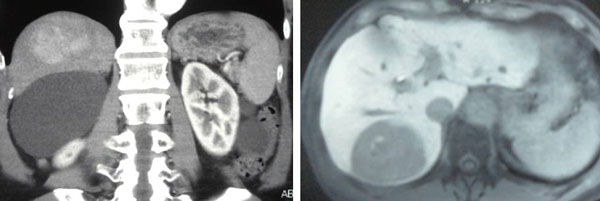

Fast forward to April 2018 – a repeat Triphasic CT scan showed:

- A solitary non-enchancing homogenous isodense liver nodule 3.3 x 3.6 cm. In view of underlying chronic hepatitis carrier, need to exclude atypical hepatocellular carcinoma.

- Associated underlying liver cysts and haemangioma.

A follow up CT in July 2020 showed:

- Increasing size and number of liver lesions in segment 2 and 3.

- Lung nodules with pleural-based lesions suggestive of lung and pleural metastases.